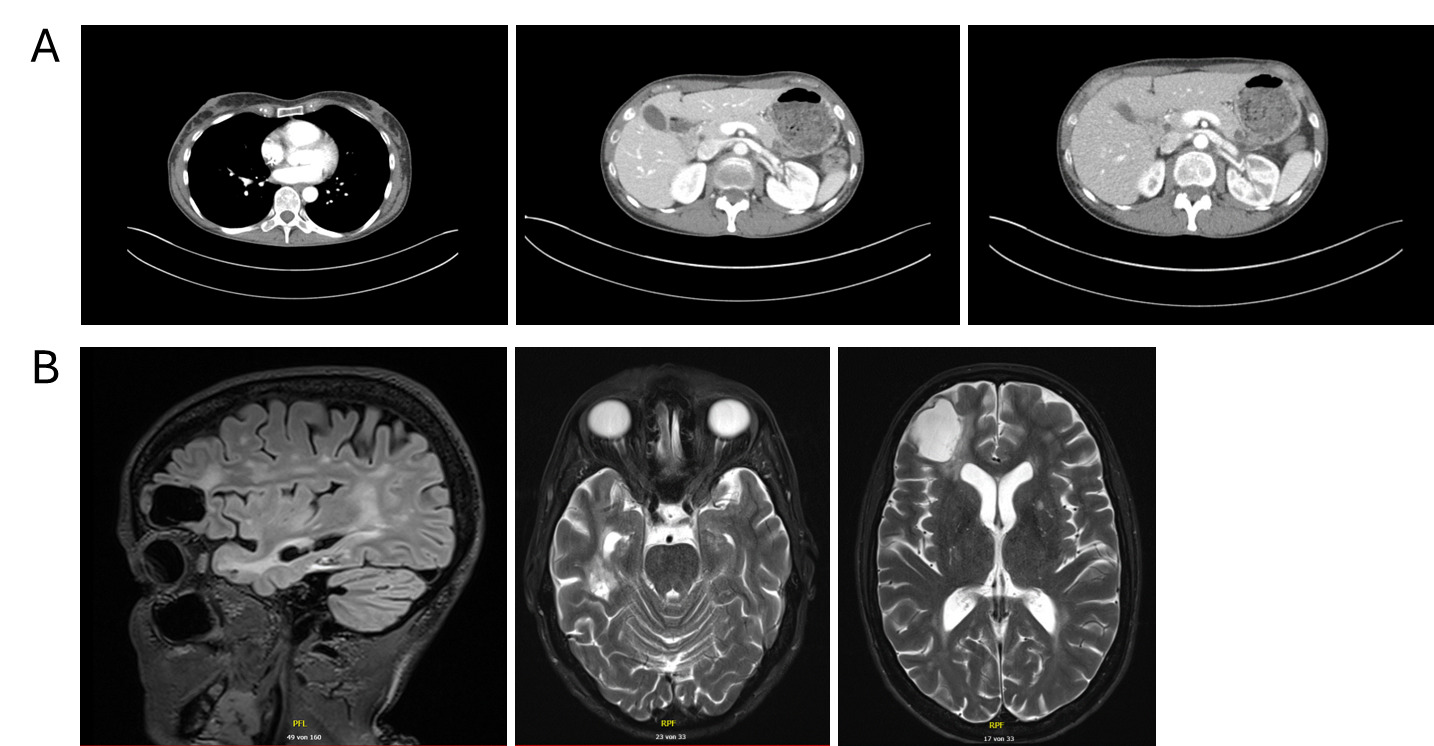

Follow-up in March 2025 showed a marked treatment response after two cycles, with significant regression of intracranial metastases on brain MRI, including resolution of midline shift and cerebral edema, as well as pronounced regression of nodal and visceral disease on contrast-enhanced CT of the thorax and abdomen (Figures 3A and 3B). No new metastatic lesions were identified, consistent with substantial partial remission.

During ongoing treatment, exulceration of the right breast primary tumor developed, indicating an early sign of further disease progression. Initially, it was managed conservatively with oral amoxicillin plus clavulanic acid and referred to specialized wound care. In May 2025, after four cycles of treatment, contrast-enhanced CT and cerebral MRI revealed disease progression involving systemic and intracranial sites (Figures 3C and 3D). Concurrently, thrombosis of the left external iliac vein and new segmental pulmonary emboli in the left lower lobe were detected and therapeutic anticoagulation with apixaban was initiated. Given the radiologic progression on paclitaxel plus pembrolizumab, carboplatin monotherapy was started as an interim measure while reimbursement approval for targeted therapy was pending. However, chemotherapy was discontinued after a single administration at the patient’s request.